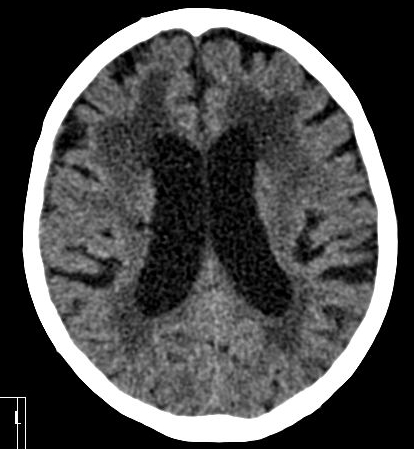

In acute phase (12-24 hours after the occlusion of the middle cerebral artery) on CT hypodense basal ganglia, the loss of cortical white-grey matter differentiation and sulcal effacement are the characteristic imaging findings.

On MRI, diffusion restriction causes hyperintense signal on T2W images. The leptomeningeal border of the infract zone will show contrast enhancement.

After 1-3 days the “mass-effect” of the infarct increases. It is more apparent in case of large territorial infarcts, the sulcal effacement completes, the loss of cortical white matter and grey matter differentiation is more pronounced (especially in the white matter) due to the increased hypodensity. Hemorrhagic transformation in the grey matter (cortex, basal ganglia) can also occur at this stage. It is worth to note, that for hemorrhagic transformation one should not always blame thrombolytic therapy; it rather occurs spontaneously in a great majority of the cases.

In the chronic phase of the infarct (months to years) the hypodensity of the lesion (CT) reaches the level of the cerebrospinal fluid. There is no more contrast enhancement, the lesion is well differentiated and it degenerates into a cyst secondary to encephalomalacia. The brain parenchyma experiences a volume decrease due to the degeneration (sometimes calcifications can occur at the marginal border of the infarct).